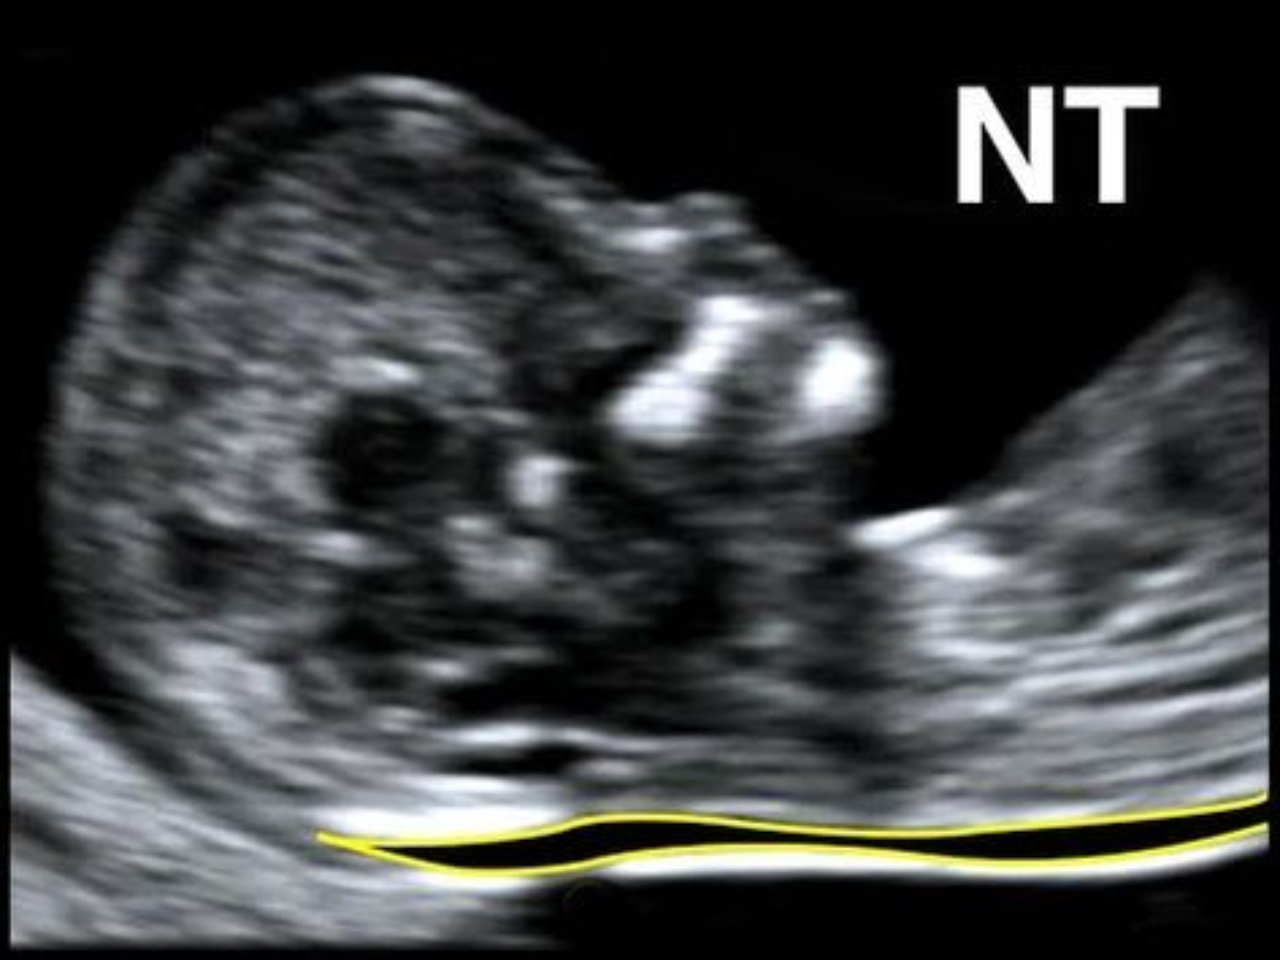

Two Simple Tests, A Lifetime of Care!

Early pregnancy is a beautiful yet crucial phase. Two simple prenatal tests — the NT Scan and the Dual Marker Test — help ensure your baby’s healthy start. [...]